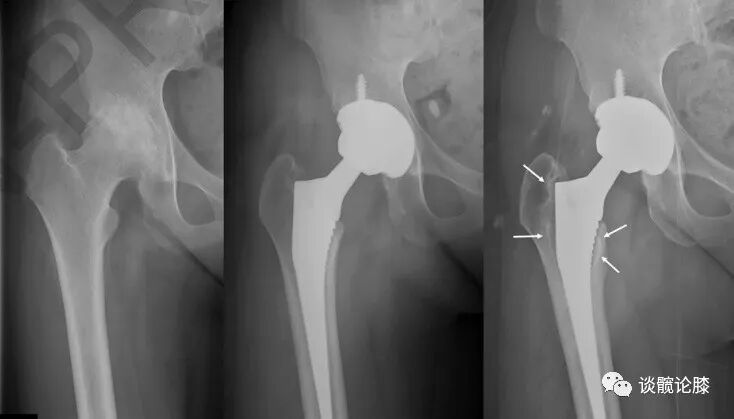

随访期间无陶瓷碎裂,5(5/85,5.9%)髋出现异响(吱吱声),3髋出现假体周围骨溶解(2髋位于股骨柄周围,Gruen分区 1和 7区,图1;1髋位于髋臼周围,DeLee -Charnley分区 2区,图2)。1例因Vancouver B2型股骨假体周围骨折而翻修(图3);1例合并系统性红斑狼疮的患者因假体周围关节感染而接受了清创术。任何原因导致再次手术的存活率为92.4%(95%置信区间为82.4%至100%)。

图2.骨溶解位于DeLee -Charnley分区 2区

图3.Vancouver B2型股骨假体周围骨折